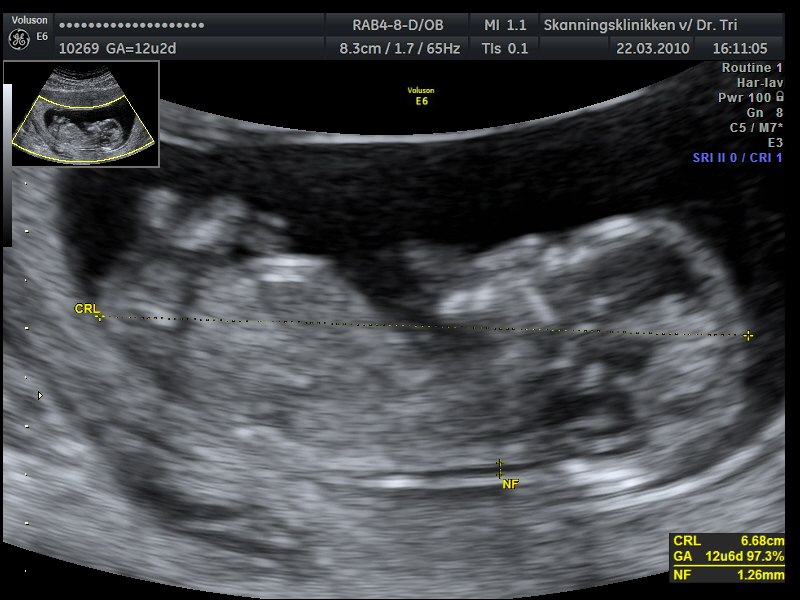

Billede 2: Nakkefold scanning